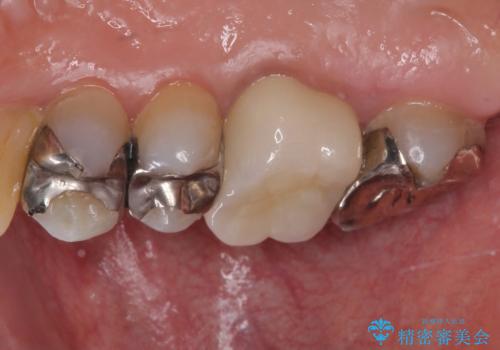

- 右上の小臼歯部に咬んだときに強い痛みを感じるとのことで来院された患者様です。

診査を行った結果、根管治療を行った後にオールセラミッククラウンにて補綴する治療計画となりました。

咬んだときの痛みに加えて夜間のズキズキする痛みもありましたが、1回目の根管治療実施後間もなく咬んだときの痛みがなくなったので、2回目に根管充填を行いました。